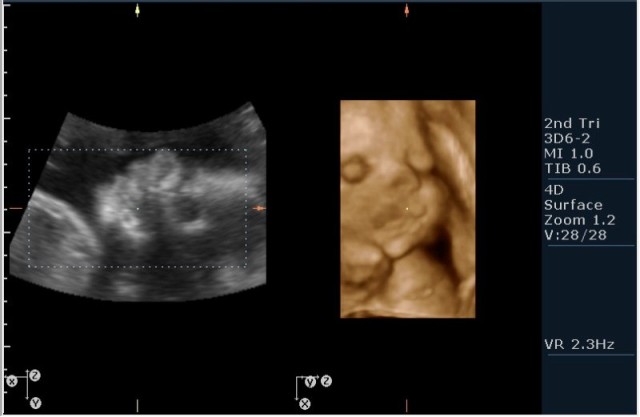

На сонограммах головы плода визуализаируется гифдроцефалия, патогенетически связанная со спинномозговой грыжей (менингомиелоцеле) представленная в 2D и 3D режимах. В режиме Skeleton не удалось получить "картинку презентационного качества", плод начал сильно вертется; но рекоммендация очень грамотная :idea: , спасибо за ваш пост!

2.V-образное расщепление позвоночного столбы(рахисхизис)(на сонограмме №6 отчетливо виден дефект в поясничном отделе);

3.наличие дорсально расположенного содержимого спинномозгового канала(на сонограмме №7 видны мозговые оболочки).Это описывается как менингоцеле.